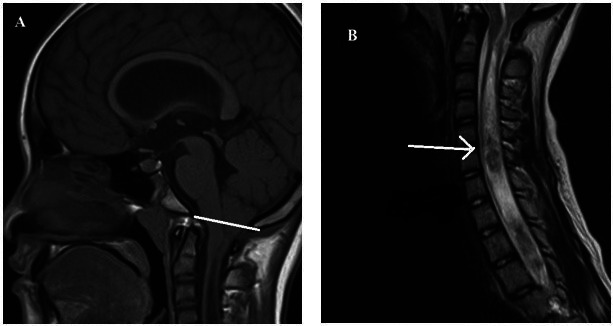

Chiari malformation type 1 (CM 1) is a rare and complex neurological condition. This congenital condition affects the lower posterior fossa, where the brain connects to the spinal cord. Although the exact cause of CM 1 remains unclear, genetic predisposition plays a considerable role in structural defects of the cerebellum. Here, we report on a 15-year-old female patient with CM 1 who exhibited both nuclear and mitochondrial genetic variants, a combination that has not been previously described. We identified a silent mutation in exon 2 (c. 556 G>A, p. Lys185=) of PAX1 and a DKK1 variant in intron 3 (548-3 t>C) in the nuclear DNA. We also screened the D-loop region of mitochondrial DNA as it exhibits a higher susceptibility to mutations than other mitochondrial DNA regions. Several hotspot variants were revealed, including those in positions 303-309 and 16519 (t>C), as well as some variants that had not been documented in MITOMAP. Our findings highlight the potential role of genetic alterations in D-loop in CM 1.